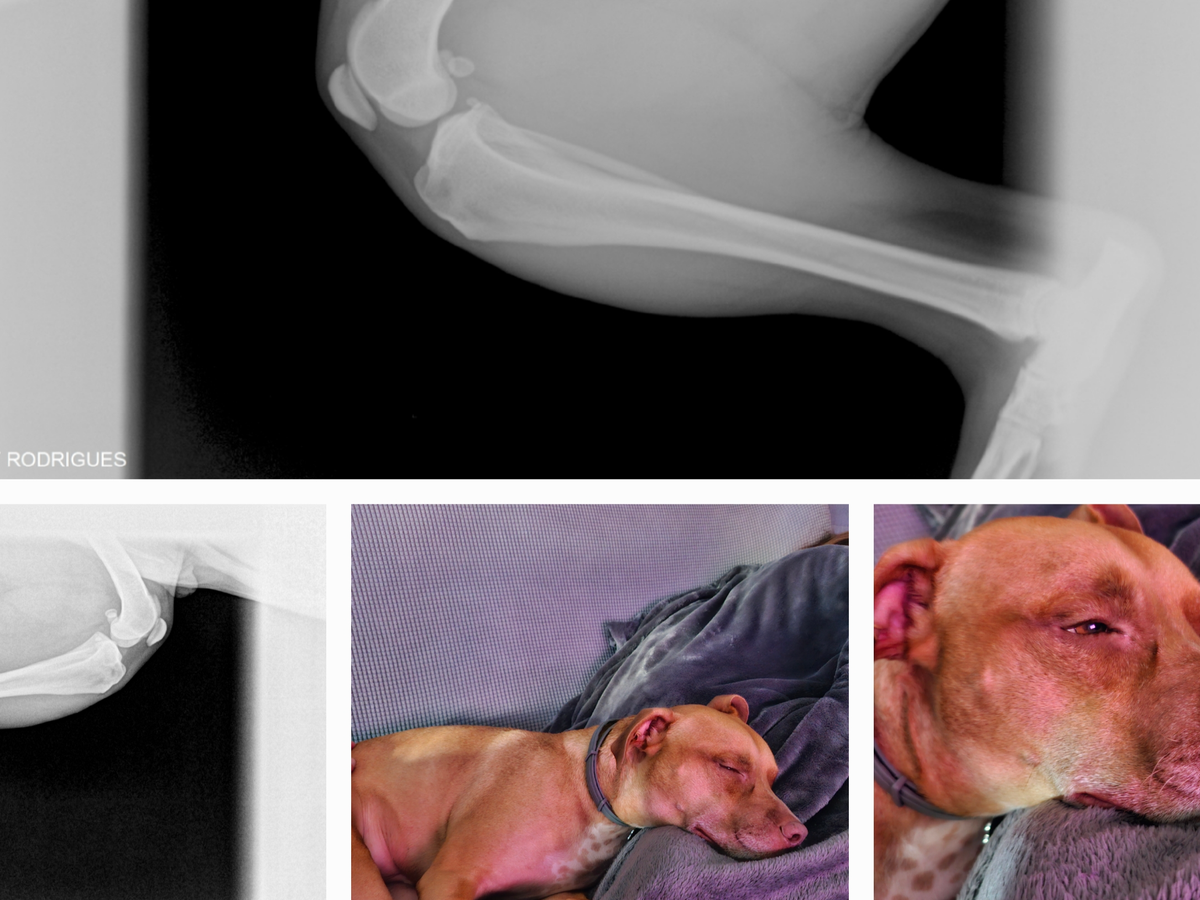

Hola me llamo Horus, he sufrido una ruptura de ligamento cruzado de mi patita izquierda y necesito operarme cuanto antes para no forzar mi otra patita y que no me pase igual, y estoy buscando echar una patita a mis papis para poder hacerlo cuanto antes, gracias a todos a los de buena voluntad.